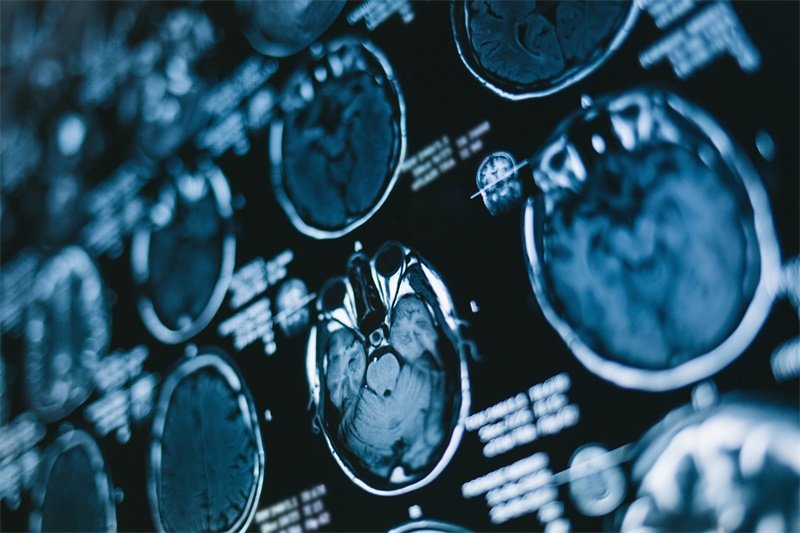

在手术前,患者需要进行影像学检查,如CT或MRI,以明确病变的具体位置及类型。麻醉医生会对患者进行全身麻醉的评估,确保手术能够安全进行。